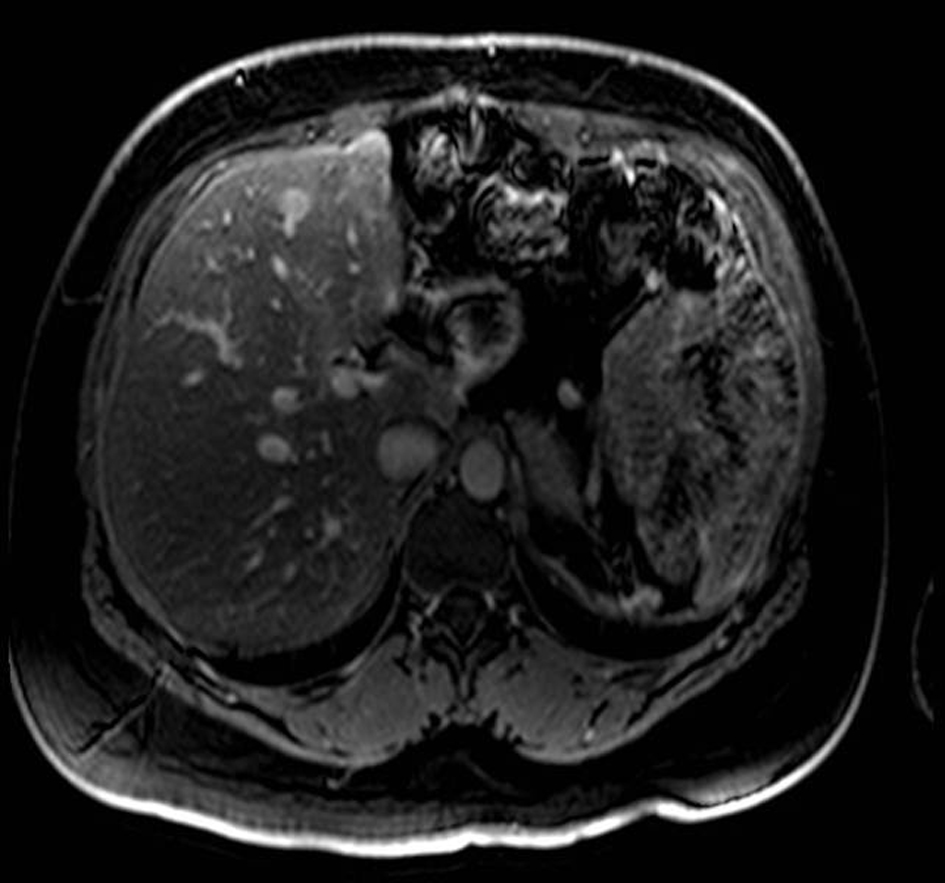

A 21-year-old female patient presented with vague left upper quadrant pain. She did not smoke or consume alcohol, and her only medication was an oral contraceptive. She appeared well, with no abnormal physical exam findings. Routine laboratory studies including liver function tests were all within normal limits. An abdominal ultrasound (AUS) revealed a large mass which appeared to originate from the tail of the pancreas. Computerized tomography-(CT)-scan demonstrated a 12 cm mass arising from the tail of the pancreas and no evidence of metastases (Fig. 1). The patient was taken to the operating room where an exploratory laparotomy confirmed that the large mass arose from the tail of the pancreas. There was no evidence of peritoneal or other distant metastases. The tumor was found to be adherent to the posterior wall of the stomach as well as to the greater omentum. A distal pancreatectomy with en-bloc splenectomy, partial gastrectomy and omentectomy was performed (Fig. 2). Pathology revealed a solid pseudopapillary tumor of the pancreas (Fig. 3), with negative resection margins. Thirteen lymph nodes were examined with the specimen, all negative for metastases. The tumor cells were positive for CD10 and alpha 1-antitrypsin, and focally positive for synaptophysin. The tumor was negative for neuron-specific enolase and chromogranin. The patient’s immediate post-operative course was complicated by pneumonia treated with oral antibiotics. She received appropriate post-splenectomy vaccinations, and was discharged home on post-operative day (POD) 7.

![]() Click for large image | Figure 3. Low power micrograph showing normal pancreas (right) and tumor (left). Note cholesterol clefts in tumor. |